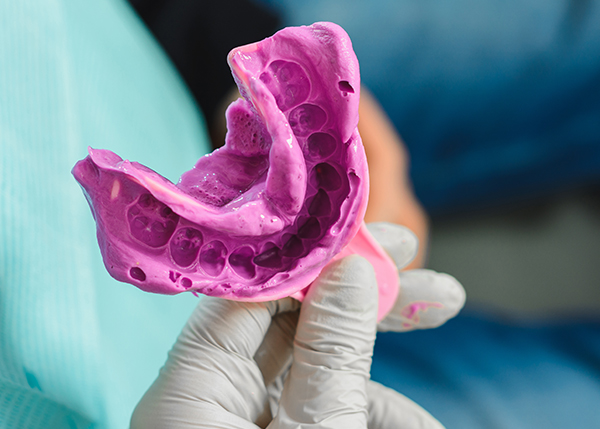

- 가글마취

- 스케일링 시 점막 표면마취를 통해

통증 완화 효과

- 도포마취

- 무통마취 주사 자입 전

통증 완화 효과

- 무통마취

- 자동 주입속도, 압력 조절로

통증 완화 효과